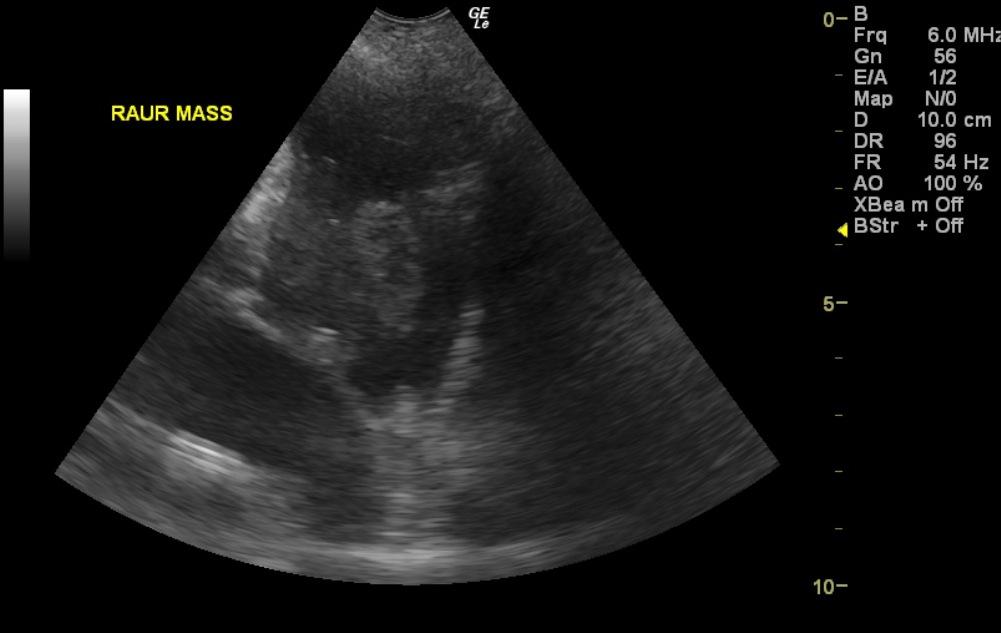

A 10-year-old SF Rottweiler cross was presented with a history of lethargy and not doing right. On physical examination depression and polypnea was evident. Abnormalities on serum biochemistry were elevated liver enzyme activity. Cardiomegaly was present on survey radiographs. Blood pressure was normal (140).